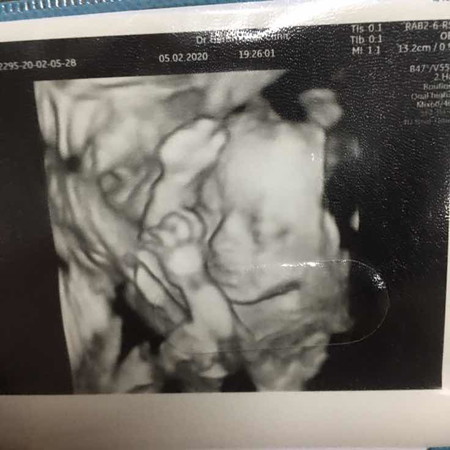

บ้านนี้ลูกชายถ่ายเอกสารจากพ่อมาเลยค่ะ☺️😊 ซาวด์ตอน24weekค่ะ

บ้านนี้ซาวตอน32wครับแม่ หมอบอกจมูกโด่งมาเลย อิอิ 🥰

วันนี้น้องครบ24wแล้ว ลุงหมอบอกว่าน้องดั้งพุ่งมากกกก.‼️??

บ้านนี้ป้าหมอก็บอกจมูกพุ่ง น้องลูกครึ่ง ไทย-อิตาลี-ฝรั่งเศส ค๊าบ ปู้จาย❤❤❤